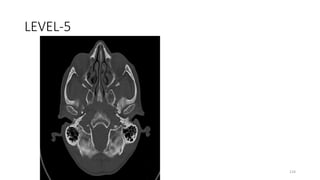

LEVEL-5

Foramen ovale

Foramen spinosum

Hyoglossal canal

Inferior orbital fissure

Occipital bone (squamous portion)

Occipitomastoid suture

Pterygopalatine fossa

Sphenoid, greater wing

Sphenoid spine (right)

Sphenopalatine foramen

Sphenosquamous suture

Temporal bone, tympanic

Tympanomastoid fissure